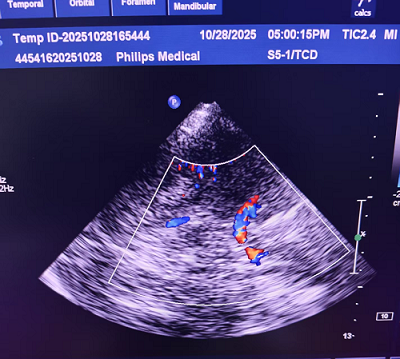

TCCD血流图